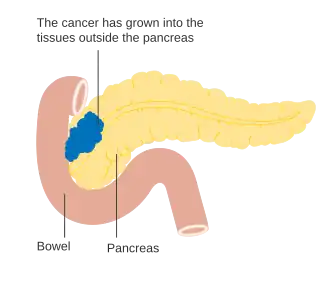

Os adenocarcinomas localmente avançados propagam-se para órgãos adjacentes, os quais podem ser qualquer um dos seguintes (por ordem aproximada de frequência): duodeno, estômago, cólon transverso, baço, glândula suprarrenal ou rim. Em muitos casos também se propagam para vasos sanguíneos ou linfáticos importantes que passem na proximidade do pâncreas, tornando a cirurgia bastante mais complexa. Os locais mais comuns de metástase (doença em estádio IV) são o fígado, a cavidade peritoneal, e pulmões, as quais se verificam em mais de metade dos casos avançados.[43]